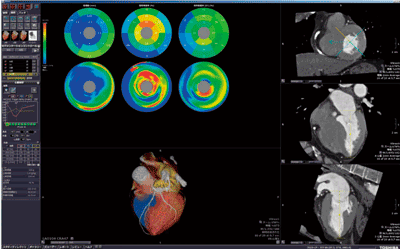

“CT Cardiac Coronary Analysis” アプリケーションは,冠動脈CTA画像から冠動脈走行状態とプラーク性状を評価することを目的としている。心臓のセグメンテーション,冠動脈の芯線トラッキング,ラベリングおよび冠動脈壁の輪郭抽出が,データ読み込み後に自動で行われる1)。1データあたり10秒程度で自動処理が完了し,心臓領域のみのVR画像,冠動脈のCurved MPR(CPR)画像等を表示することができる。ユーザーによる作業の手間を省き,診断上有益な画像を得るまでのスループットが高いのが特長である。

観察に関しては,CPR画像等の冠動脈解析特有の表示と,MPR 3断面表示も可能であり,虚血領域と責任血管の関係把握に効果的である(図2)。解析に関しては,自動で抽出された冠動脈の内壁および外壁の輪郭を用い,CT値情報を基にした冠動脈壁内のプラーク性状分析を行うことができる。また,芯線上で注目したい範囲を指定することで,冠動脈の内腔径,面積,体積および狭窄率などの幾何学的なパラメータも算出することができる。解析した結果は,冠動脈解析専用のレポートに自動的に引き継がれ,検査全体のスループット向上をサポートしている。

図2 CT Cardiac Coronary Analysis解析例(図1と同症例)

(画像ご提供:相澤病院様)